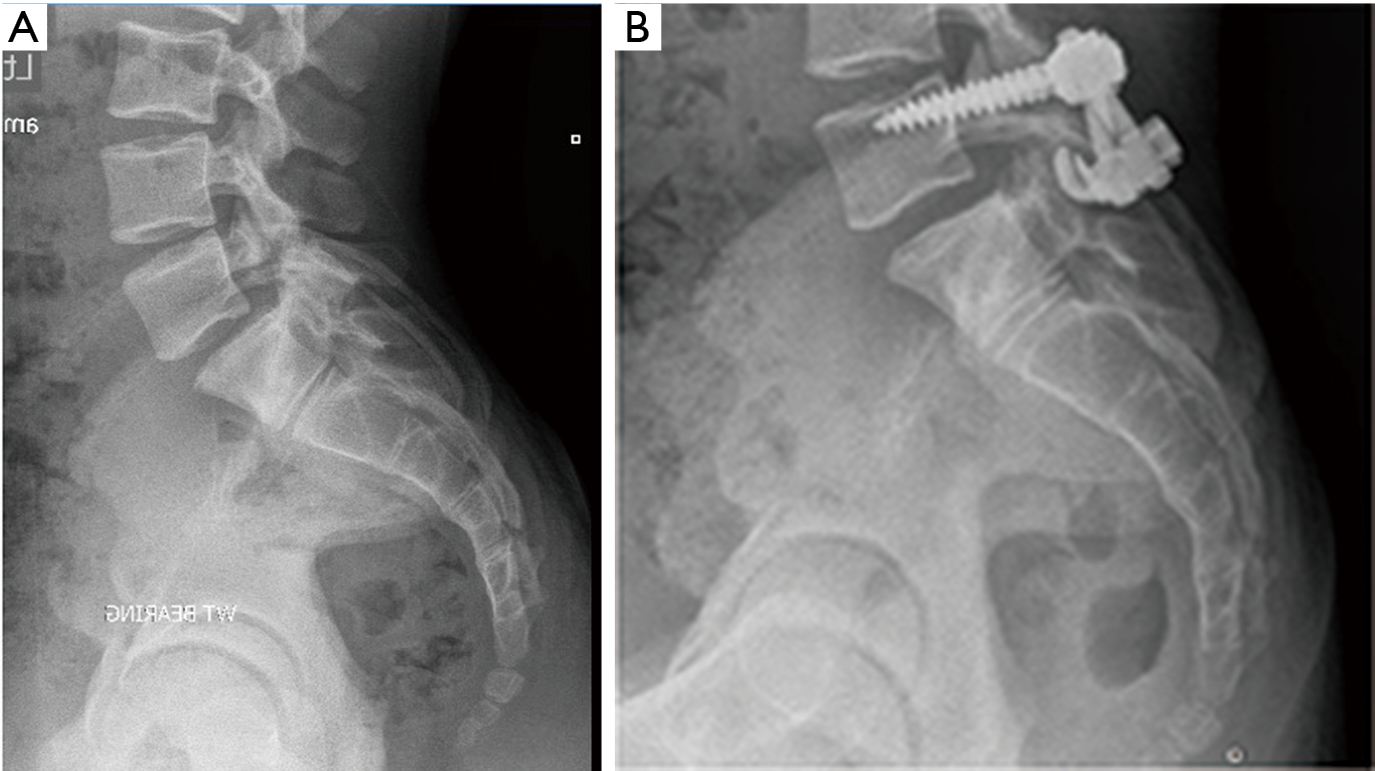

Spondylolisthesis surgery image This image demonstrates Spondylolisthesis surgery.

Fashionable 1965 7 results from hyperextension of the upper external body part spine. And the consistence parts which undergo sensation through l4 spinal nerve let in knee, thigh, ramification and foot. Objective: to present an special case of Associate in Nursing isolated lamina break in the external body part spine found away taking stress films when a unremarkable cervical series failing to demonstrate it. 7 for the posterior approach, the important anatomical landmark is the sacral foramen, which corresponds to the posterior posterior opening at the end of the sacral canal, commonly located at the fifth sacral vertebra. The coflex device is made of Ti alloy and comes in . The wreath facet orientation of l5-s1 and lumbosacral joint angle explains the reason wherefore traumatic spondylo-listhesis occurs mostly on l5-s1 level.